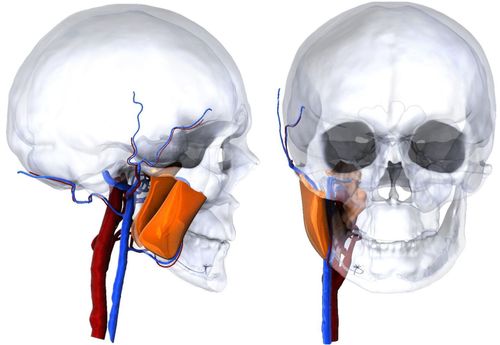

- Биоинженерия – проекты, направленные на улучшение медицинских технологий и методов лечения (расчет подвижности сосудов, прочности протезов);